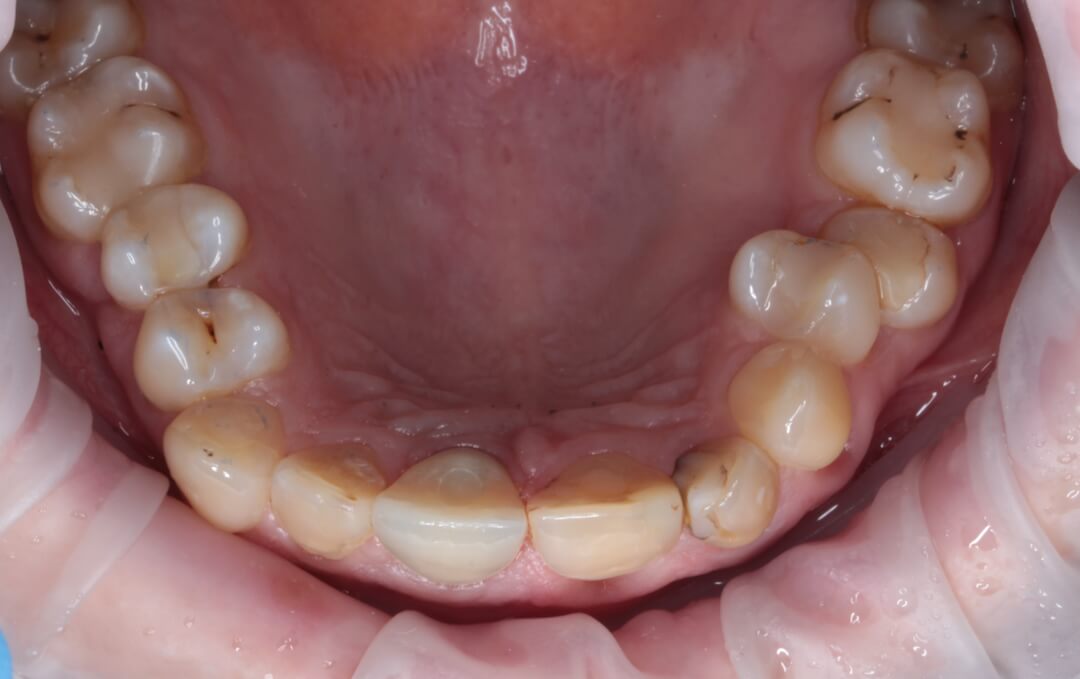

Рис. 4. Вид временной коронки на винтовой фиксации с окклюзионной поверхности. Шахта титанового абатмента закрыта фотополимеризационным материалом.